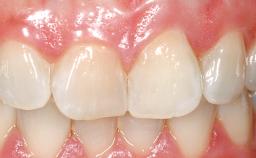

A 42-year-old female patient was referred to our clinic at the School of Dentistry of the University of São Paulo in November 2004, presenting a deficient restoration in the upper left central incisor. The clinical examination revealed no gingival retraction or any signs of gingival inflammation and, therefore, previous periodontal treatment was not considered. The patient presented a high lip line at full smile and a thin tissue biotype. This combination characterized a high-risk situation from an anatomic point of view, which required careful preoperative planning and cautious surgical execution.

Lip Line No exposure of papillae Exposure of papillae Full exposure of mucosa margin

Periodontal Phenotype Low-scalloped, thick Medium-scalloped, medium-thick High-scalloped, thin

Soft Tissue Contour and Volume Ideal